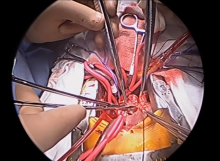

In 1984, Nikaidoh described the concept of aortic translocation for the management of transposition of the great arteries (TGA) with a ventricular septal defect (VSD) and pulmonary stenosis (PS). Patients with TGA/VSD/PS or double-outlet right ventricle (DORV) with malposed great vessels and PS who also present with a restrictive or inlet-type VSD, a hypoplastic right ventricle, or a straddling atrioventricular valve benefit the most from this complex procedure. This surgical technique avoids the creation of a long and tortuous intraventricular tunnel, as seen with the Rastelli procedure. It also creates more normally aligned right and left ventricular outflow tracts (RVOT and LVOT), which reduces the risk of recurrent LVOT obstruction and compression of the right ventricle (RV) to pulmonary artery (PA) connection by the sternum.

In the author’s opinion, the most important intraoperative surgical decisions include the management of the coronary arteries during aortic translocation (harvesting from the aortic root or not) and the reconstruction of the RV to PA connection (conduit, pulmonary root translocation, or direct PA to RV connection). When the great vessels are side-by-side, at least one of the coronary arteries needs to be reimplanted during translocation, but when they are anterior–posterior, commonly both coronary arteries can be left attached. Avoiding coronary ischemia is extremely important for a successful outcome. Also, the avoidance of an RV to PA conduit appears to reduce the incidence of reoperations.